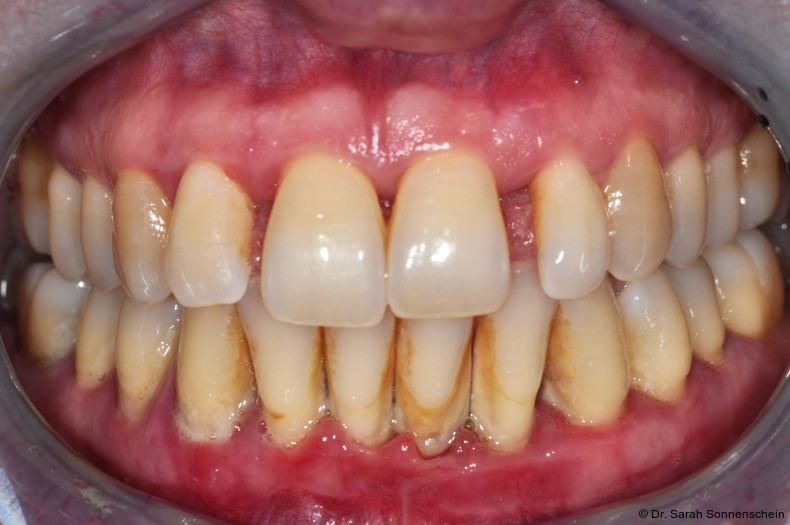

Die Abbildungen 2a–d zeigen die Eingangssituation einer allgemeinmedizinisch gesunden 37-jährigen Nichtraucherin mit Parodontitis Stadium IV Grad C, Falltyp 1 (damalige Diagnose: generalisierte aggressive Parodontitis). Ihr Hauptanliegen war der Zahnerhalt und die Beseitigung der „lockeren“ Zähne. Die Sondierungstiefen lagen generalisiert zwischen 5 und 9 mm. Die AV bei bis zu 12 mm. Die Zähne 33-43 wiesen alle einen Lockerungsgrad III auf. Auch die Oberkieferfront wies einen Lockerungsgrad II auf. Nach der Mundhygienephase erfolgte eine Full-Mouth-Disinfection mit adjuvanter Antibiotikagabe. Die Schienung der Zähne 33-43 erfolgte mittels glasfaserverstärkter Kompositverblockung. Bei Befundevaluation zeigten sich nur noch vereinzelte Taschen von bis zu 5 mm, welche reinstrumentiert wurden. Die Patientin konnte entsprechend in die engmaschige UPT (dreimonatiges Intervall) überführt werden. Zur Verbesserung der Ästhetik und Stabilisierung der gelockerten Oberkieferfrontzähne erfolgte nach Abschluss der aktiven Behandlungsphase ebenfalls eine Verblockung der Oberkieferfrontzähne und Zahnumformung im direkten Verfahren mittels Komposit. Abbildungen 3a–d zeigen die Situation der Patientin zweieinhalb Jahre nach Erstbefundung.